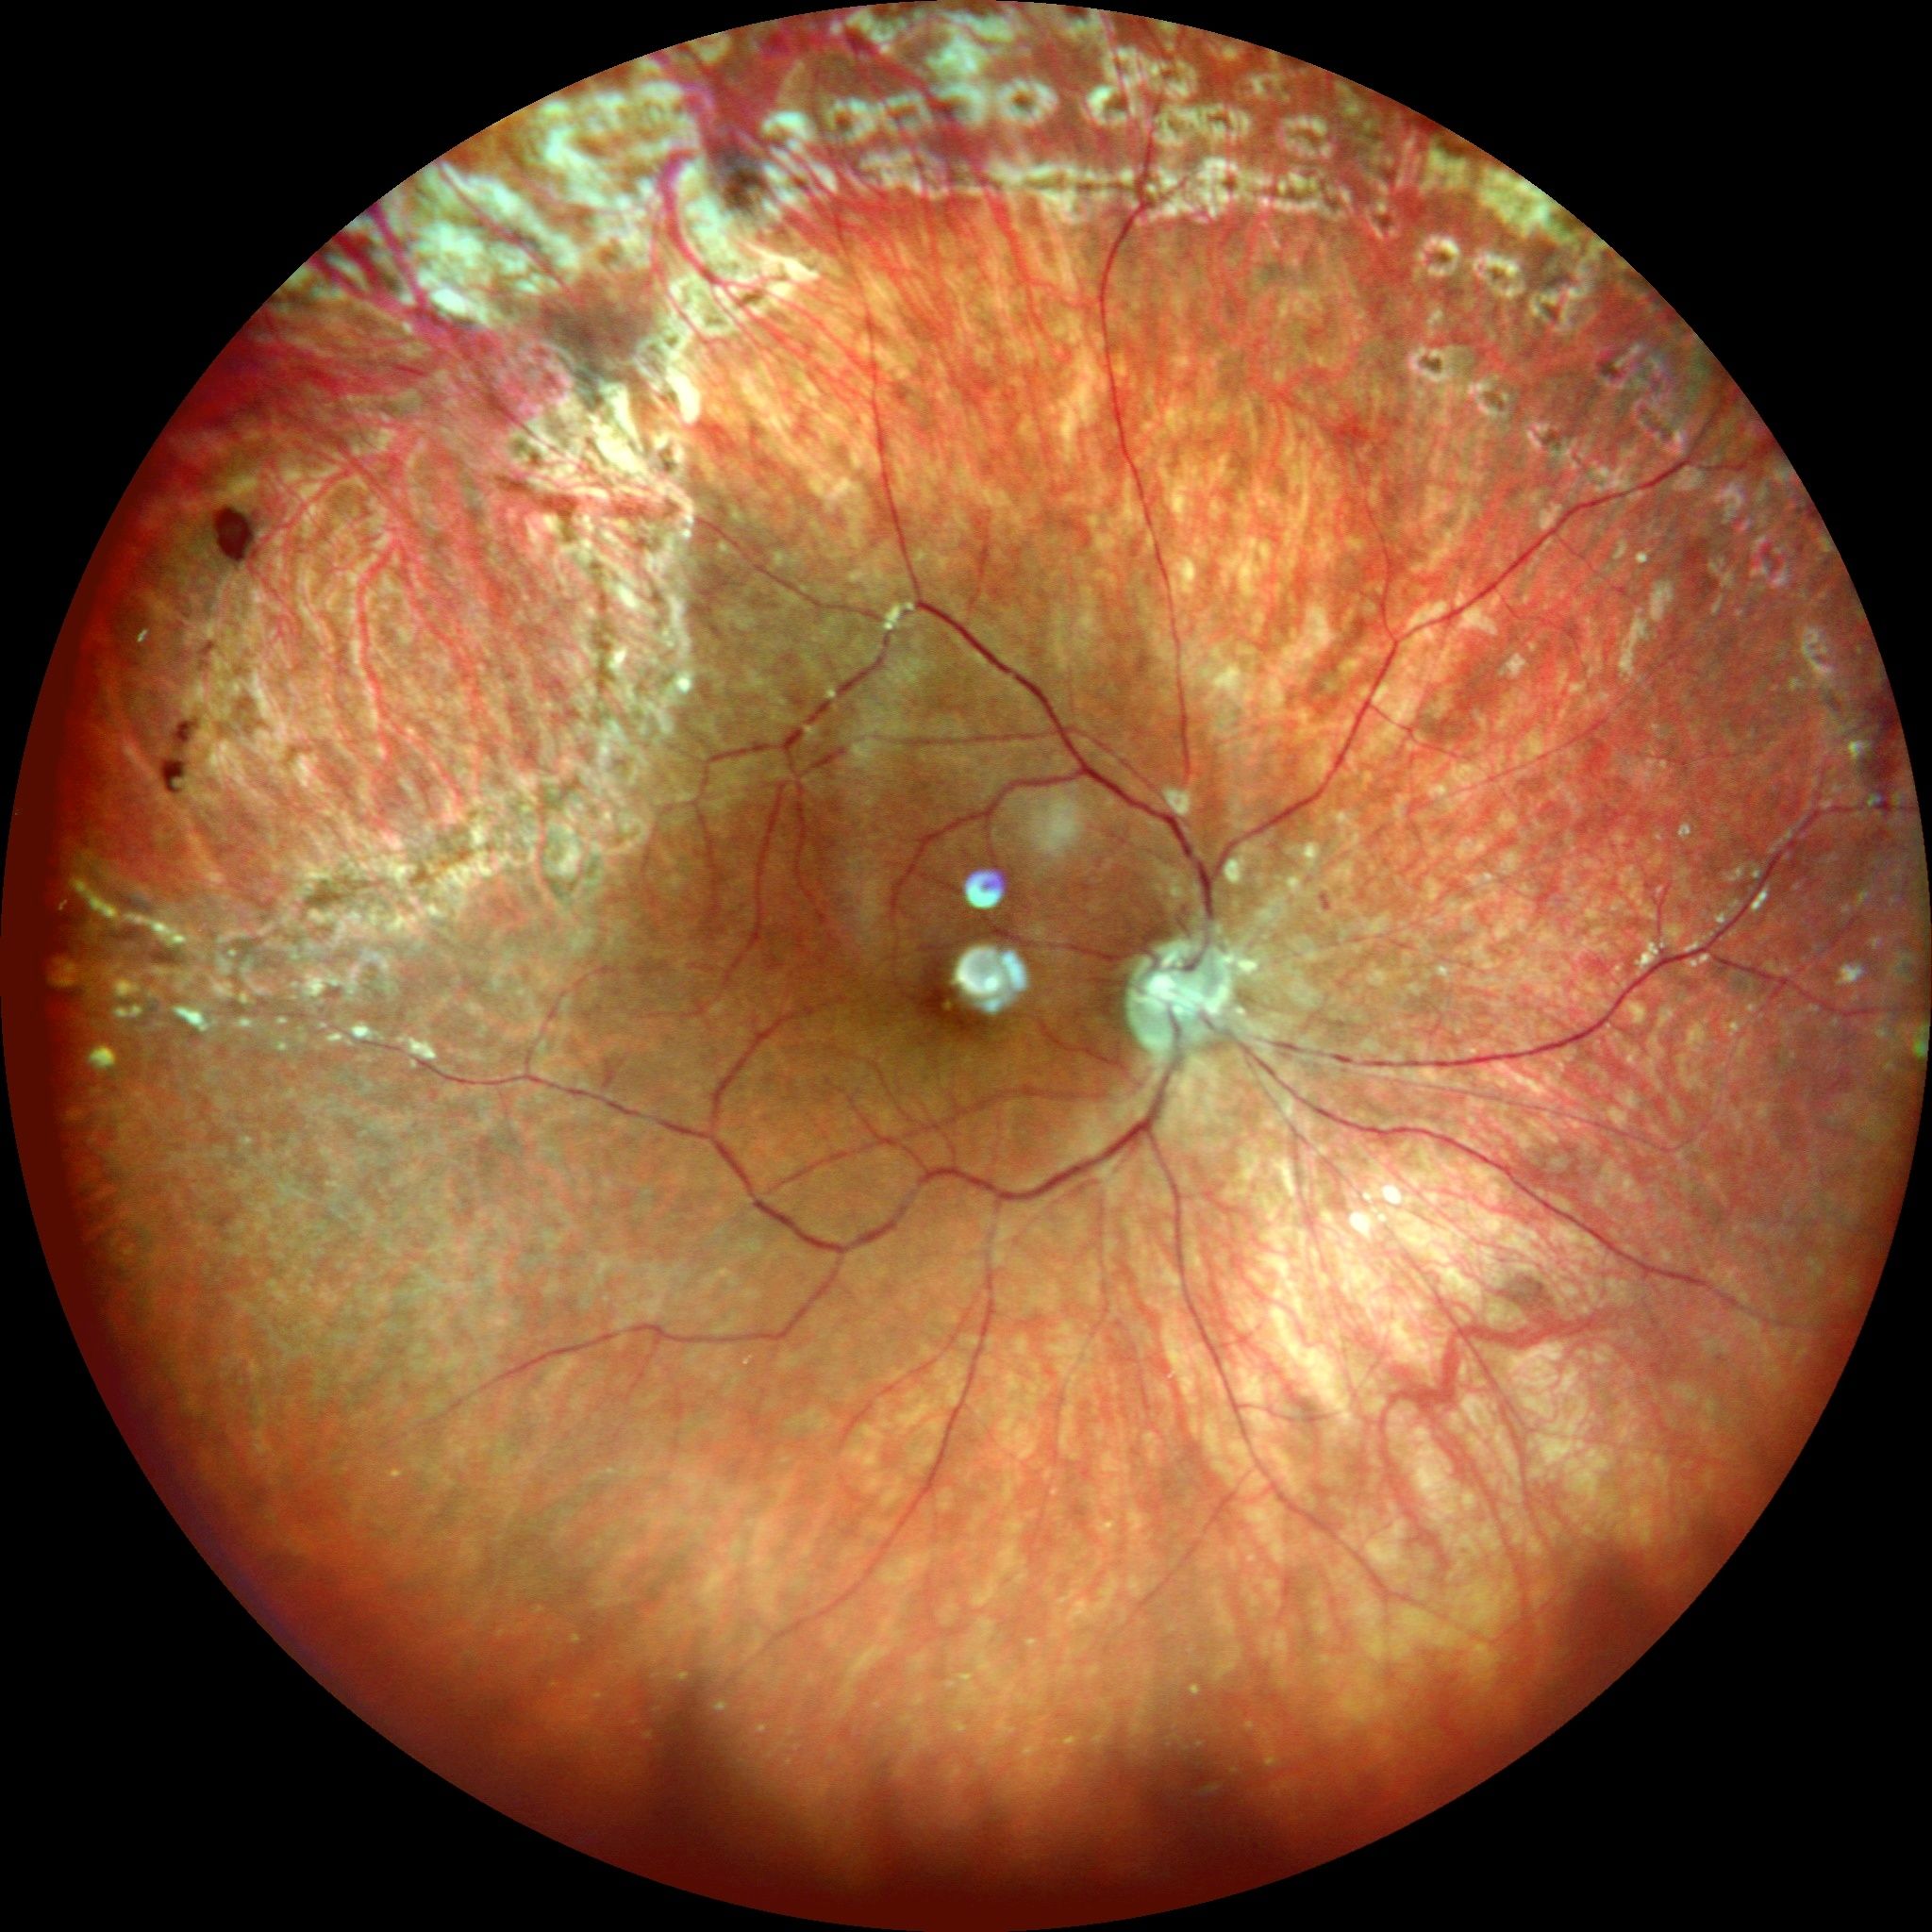

Sağ gözde büyük at nalı yırtığa bağlı gelişmiş olan büllöz retina dekolmanı.Ameliyat öncesi, pars plana vitrektomi ve gaz injeksiyonundan 2 ay sonraki geniş açılı gözdibi görüntülemesi ve ameliyat sonrası maküladan alınan OCT kesiti.